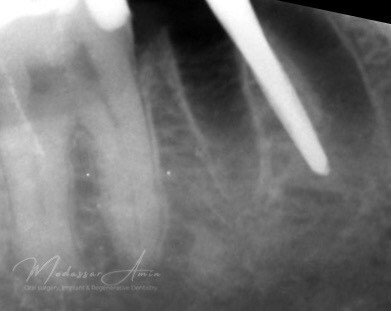

PATIENTFALL

"Pasienten presenterte med tann 46 som ikke kunne bevares grunnet en dyptgående infraksjon inn i furkasjonen. Forholdene lå til rette for en immediate implantatbehandling. Ved hjelp av Versah osseodensifikasjonsbor ble det interradikulære beinet ekspandert på en skånsom og forutsigbar måte, noe som ga høy primærstabilitet (>40 Ncm) til tross for en lokal bendefekt apikalt mesialt etter kronisk apikal periodontitt. Den gode stabiliteten muliggjorde bruk av SSA (Sealing Socket Abutment) for forsegling. På grunn av tynn bløtvevsfenotype bukkalt ble behandlingen supplert med bindevevstransplantat (CTG)"

Kontrollröntgen implantat

Kontrollröntgen SSA